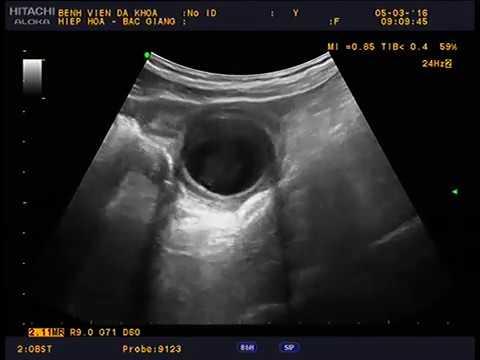

- Siêu âm: Là phương pháp ban đầu thường được sử dụng để phát hiện sự hiện diện của u nhầy.